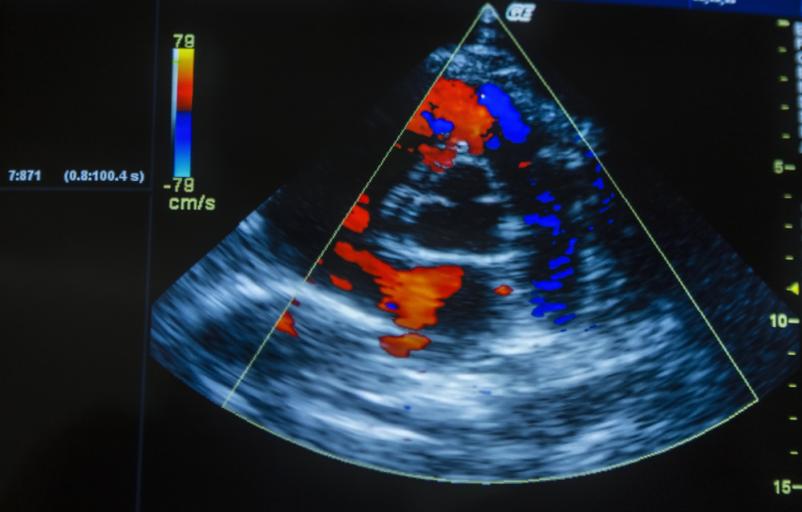

Ultrazvočni pregled srca je ena ključnih diagnostičnih preiskav v kardiologiji. Ultrazvok srca v Ljubljani in okolici omogoča oceno srčne mišice, zaklopk in pretoka krvi, kar zdravnici nudi vpogled v delovanje srca v realnem času.

Preiskava poteka brez sevanja, je neboleča in varna. Pacient med pregledom leži na boku, zdravnica pa s sondo pregleda srce iz različnih kotov. Celoten postopek običajno traja približno dvajset do trideset minut in ne zahteva posebnih priprav.